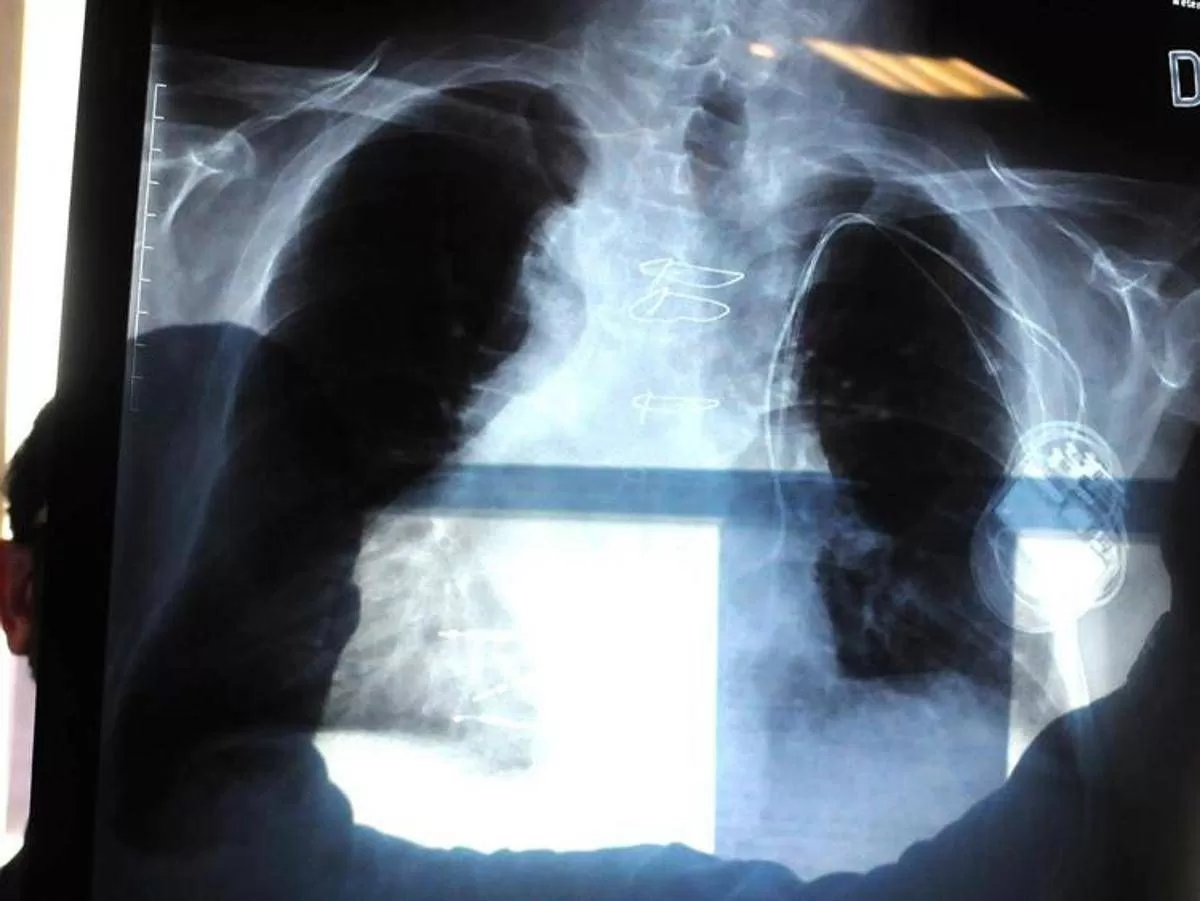

La polmonite, prosegue il presidente di Aipo, è un’infezione che “può essere localizzata in un punto particolare del polmone. L’ente patogeno più frequente in questo caso è lo pneumococco, contro il quale esiste appunto una vaccinazione. Esistono poi le polmoniti interstiziali che colpiscono il tessuto connettivo del polmone, l’area dove avviene lo scambio, per questo l’infezione può essere molto diffusa e anche bilaterale. E’ dovuta prevalentemente a virus, il Covid tra questi, come abbiamo visto durante la pandemia, e ad alcuni batteri. Altro caso abbastanza emblematico è la legionella, oppure i cosiddetti agenti intracellulari, micoplasma e clamidia”. L’intestizio, precisa Micheletto, “è il tessuto di sostegno del polmone, dove avviene il passaggio dell’ossigeno e dell’anidride carbonica nel senso contrario, tra gli alveoli e i capillari. Quando questo interstizio viene colpito, lo scambio viene notevolmente ridotto. Ma se il paziente ha la bronchite cronica o è un fumatore, questi spazi sono già compromessi. E quindi può dare casi gravi”.